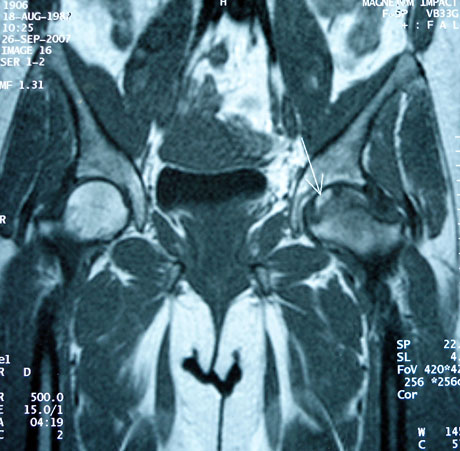

MRI: left femoral head osteonecrosis (white arrow)

Aseptic non-traumatic osteonecrosis of the femoral head is a painful disorder in which there is subchondral bone death due to insufficient vascular supply that can lead to femoral head colapse and the need finaly for total hip replacement. Affecting young patients and their most productive age. The pathogenesis of the disease is unknown. As osteonecrosis may be a disease of mesenchymal stem cells, the possibility has been raised than bone marrow containing osteogenic precursor implanted into the necrotic lesion could be of benefit in this condition.